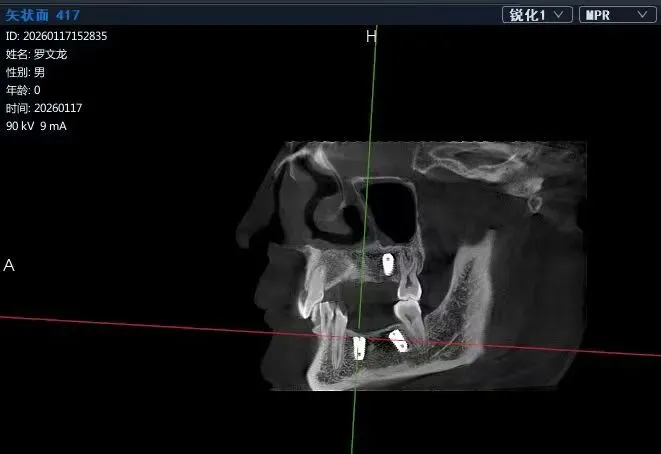

Case:患者罗某,男,种植一期术后因故未按时复诊,六年后来院复查,植入区CT影像如下:

图1:34CT冠状面

如图1、图2影像所示:植体上方有1-2mm厚的皮质骨覆盖,二期手术中应该去除阻碍覆盖螺丝脱位的牙槽骨,覆盖螺丝才易脱位。而在实际手术过程中,临床医生由于病情预估不到位或者操作经验不足,在未清除妨碍覆盖螺丝脱位的牙槽骨时强行反旋覆盖螺丝,导致覆盖螺丝六角冒丝,之后采用多种方法尝试取出未成功。本人多点执业救急,采用如下方法取出,未伤及植体,患者后期成功修复。